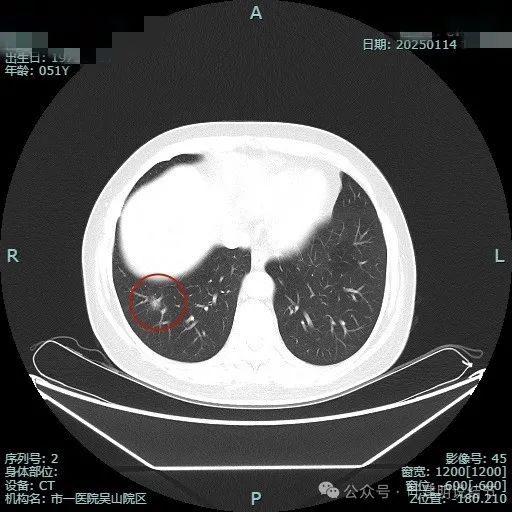

再看在我门诊时2025年1月14号复查的靶扫描影像:

非薄层上见病灶混合密度,整体轮廓较清。

薄层上见病灶表面有毛刺征。